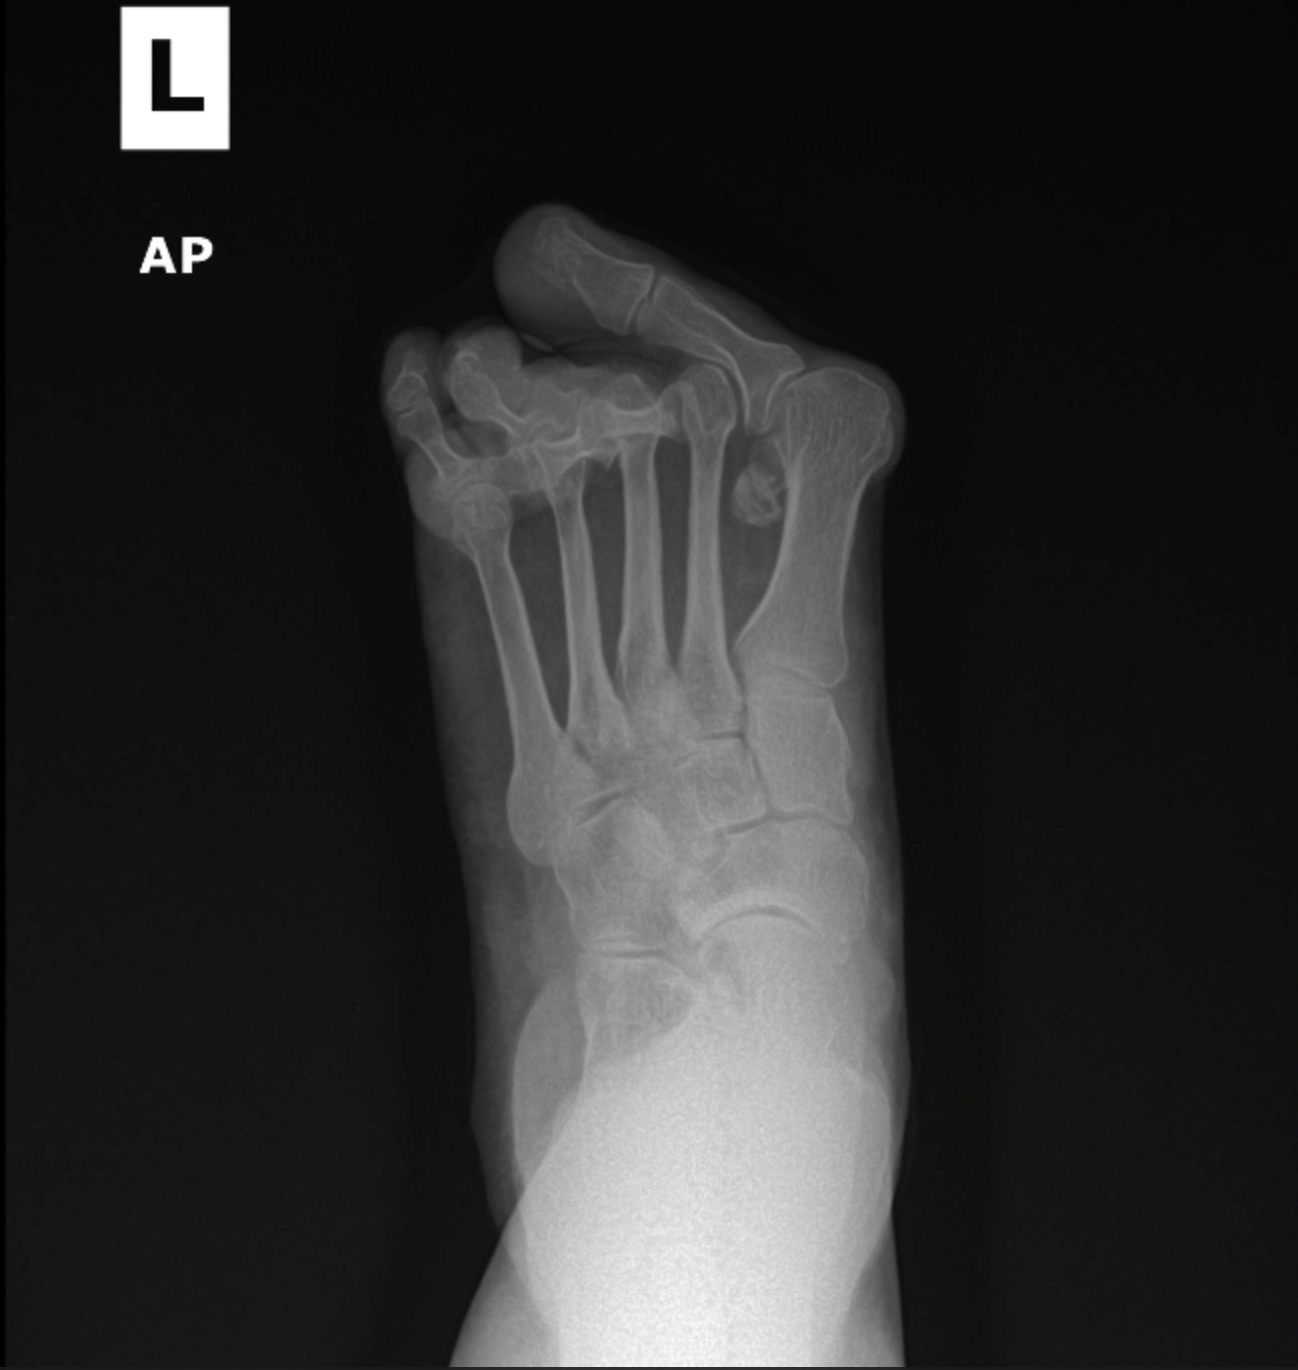

Rheumatoid foot

Pre and post XRS for severe rheumatoid foot pre and post XRS